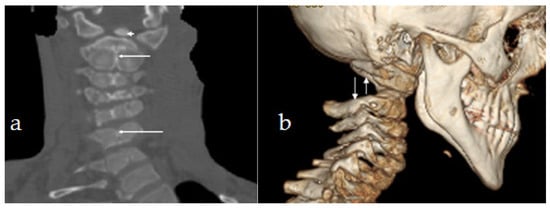

AP cervical and upper thoracic spine of a 16-year-old girl with pseudoachondroplasia showed torticollis associated with unusual flattening of the cervical spine. The MRI has illustrated the remnant of the persisting dentocentral synchondrosis. The localisation and level of the remnant of the dentocentral synchondrosis, started from the detached odontoid process and extended downwards to involve the entire cervical spine (as part of a generalised cervical spine synchondrosis (Figure 3a,b). Not only is this anomaly an important anatomical detail, but it is also very relevant from a clinical perspective because of the odontoid and C2 fractures.

Figure 3. (a,b) AP cervical and upper thoracic spine of a 16-year-old girl with pseudoachondroplasia showed torticollis associated with unusual flattening of the cervical spine (arrow). The MRI has illustrated odontoid dysplasia (arrow head) the persistence of dentocentral synchondrosis (arrow). The localisation and level of the remnant of the dentocentral synchondrosis started from the detached odontoid process and extends downwards to involve the entire cervical spine.